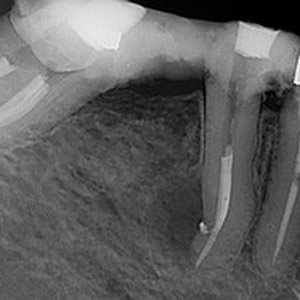

NON-SURGICAL

Oftentimes, our patients need non-surgical treatments that require minimal intervention. This intertwines with our belief that preventative maintenance and regular dental care can minimize the need for surgeries. You can rest assured that our highly trained and experienced team consistently provides the highest quality endodontic treatments and assistance available in the North Shore.